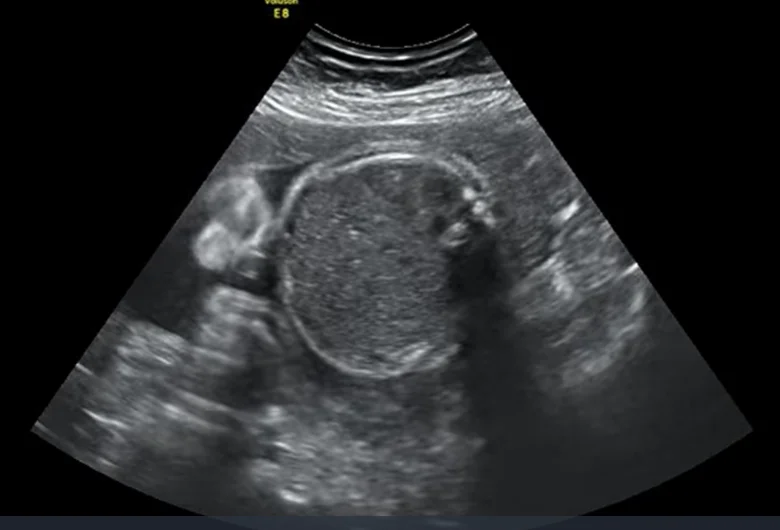

Nang phế quản thai nhi (Bronchogenic Cyst)

• Nang phế quản thai nhi (Bronchogenic Cyst)